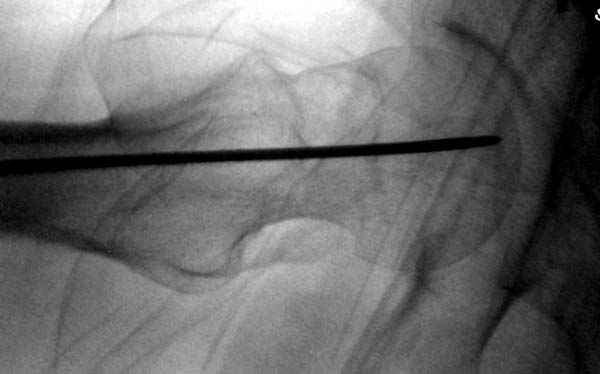

Профилактику дальнейшего раскола неполного перелома шейки провели тремя канюлированными шурупами.

Наверное речь идет насчет parallel guide из набора. Применяем по возможности всегда, но,

как видно на снимке, не всегда получается

паралельно.

Такие несмещенные переломы обычно для молодых резидентов, и бывают технические неточности, но в этом случае посчитали фиксацию адекватной.

Соблюдая правила, многократными попытками можно

увеличить риск стрессового перелома латерального

кортекса.